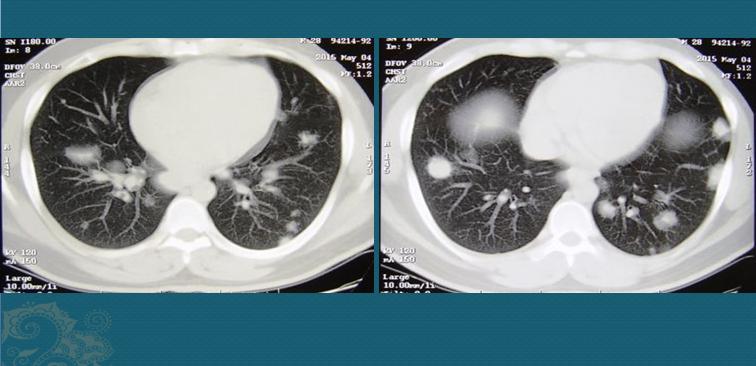

1.一位28岁的年轻人,间断性咳嗽,于是做了个胸部CT:

CT发现他双肺长了10多个圆形结节,最大的超过2厘米。

分为肺泡结节病、肉芽肿结节及肺纤维化。可以表现为边缘模糊的斑片影或者磨玻璃影、网格状影(如下图),其内可见含气支气管,两肺上叶多见;或者呈形状规则的小结节(多数大小2mm-1cm),多沿支气管血管束和小叶间隔、叶间裂、胸膜下的淋巴管网分布,以肺野中带及胸膜下较为明显,如上图第一位小伙子,不要误诊为转移瘤。